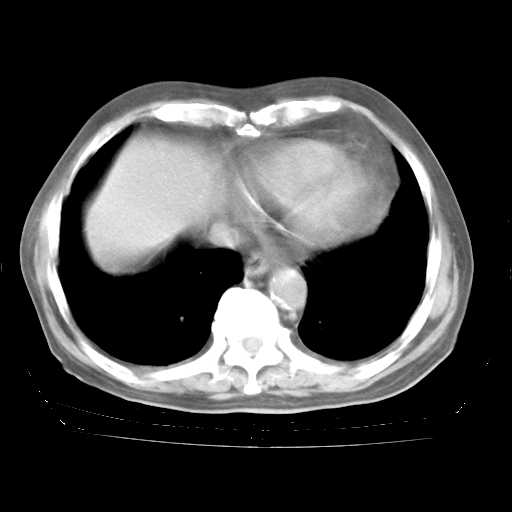

4月28日肺部CT——再次出现类似去年5月9日——透光度降低,“间质性”改变。

4月28日肺部CT——再次出现类似去年5月9日——磨玻璃样、间有“粟粒样”改变。

个人阅读4.14日肺部CT平扫:纵隔窗无异常,但肺窗示:双下肺内、后基底段有片絮状侵润影,部位以后基底段为著,以间质改变为主,呈急性肺泡炎征像,和首次住院影像学有相似之处。仅是个人读片,明日请相关专家再读片哈。其它建议同上。